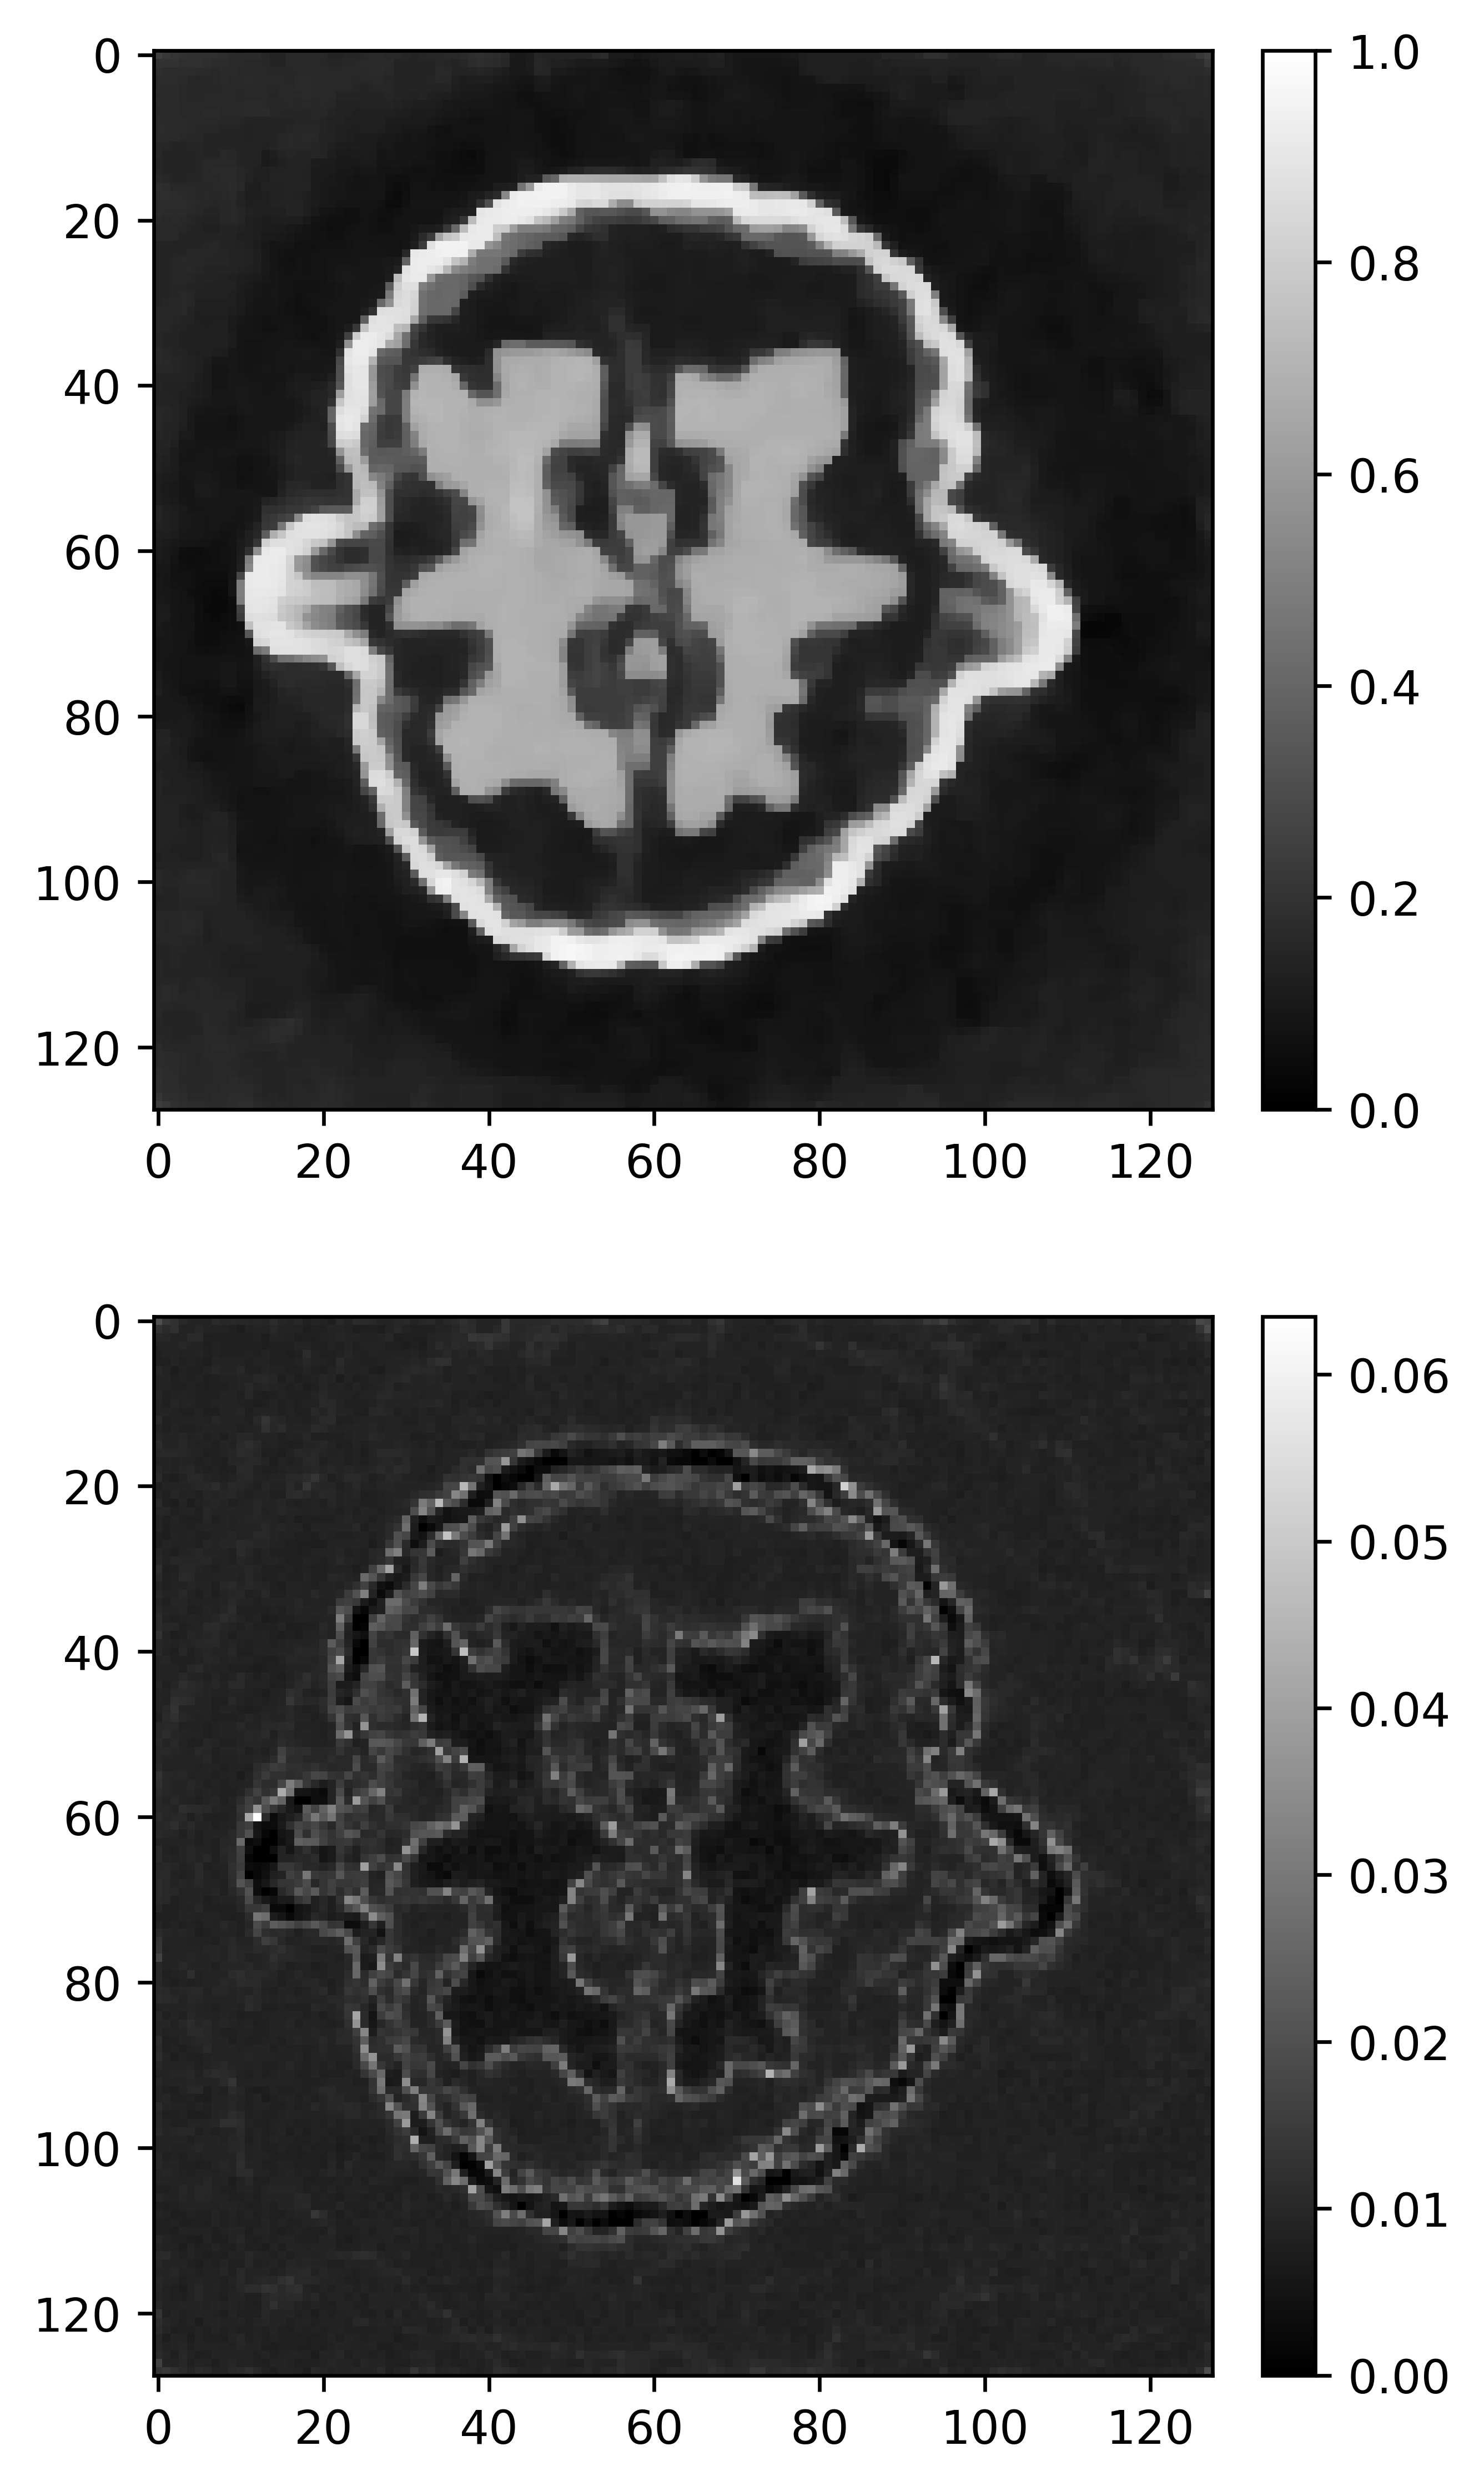

Refer to caption

(a) Gibbs-BPS

(b) PLD

Figure 10: Comparison of CT reconstruction for Lung CT Image 2 with fused L1/2L_{1/2} prior and fused LASSO prior. The upper images are posterior mean. The bottom images are posterior standard deviations.

Table 4 and Figure 7 compare the convergence speed of MCMC algorithms for large-scale images. We see that when dealing with high-resolution images, the advantages of Gibbs-BPS become evident. It is the most efficient for Walnut Phantom with 128×128128\times 128 pixel, then followed by Gibbs sampler and PLD. The pCN has the slowest convergence speed. For two lung CT images with 256×256256\times 256 pixel, the Gibbs sampler does not work due to the inability to sample the Gaussian distribution with dimensions 2562256^{2}, and we also found that the pCN suffers from numerical instability. The proximal Langevin dynamic is the only competitor for the problem with size. In this case, the Gibbs-BPS converges slightly faster than PLD. Figures 8-10 show the posterior statistics for the three high resolution images recovered by various methods. For Walnut Phantom, the image recovered by all the methods except for edge-preserving horseshoe prior have the similar quality. For two lung CT images, the fused L1/2L_{1/2} prior always did slightly better than the fused LASSO prior in terms of PSNR. The posterior standard deviation estimated by the PLD algorithm is much smaller than Gibbs-BPS. Since this phenomenon consistently holds for all the scenarios for PLD, we suspect that the PLD may underestimate the posterior standard deviations.